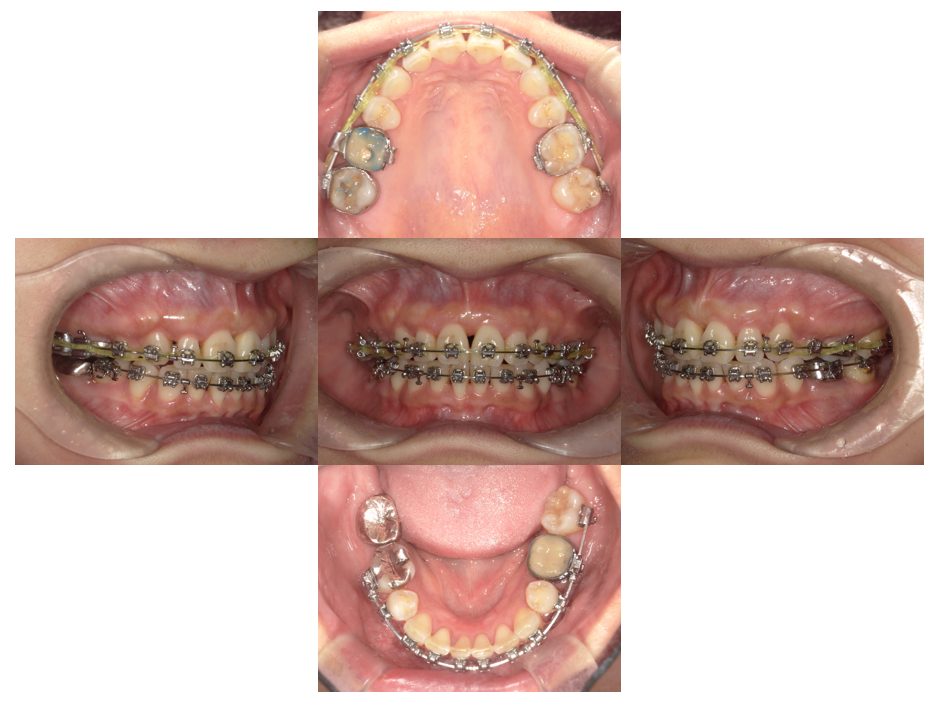

| 主訴 | 過去作成した右下の被せ物がずれて入っており、たまに腫れる。歯並びも気になる。 |

| 治療内容 | 矯正治療を行いました。 |

| 治療費 | 800,000円(税込み) |

| 治療期間 | 2年半(矯正治療期間 2年) |

| 治療回数 | 30回 |

| 想定されたリスク | 術前に基礎資料を整え分析し、セットアップモデル等でシミュレーションをしておかないと、予定通りの治療が行えないリスクがあった。 |